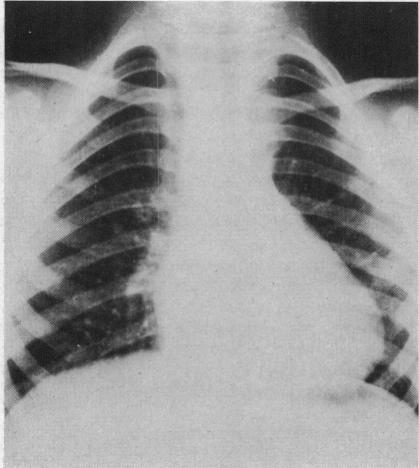

MULTIPLE INJECTIONS FOR ANGIOCARDIOGRAPHY.

Br Heart J. 1965 May;27(3):333-43. doi: 10.1136/hrt.27.3.333.